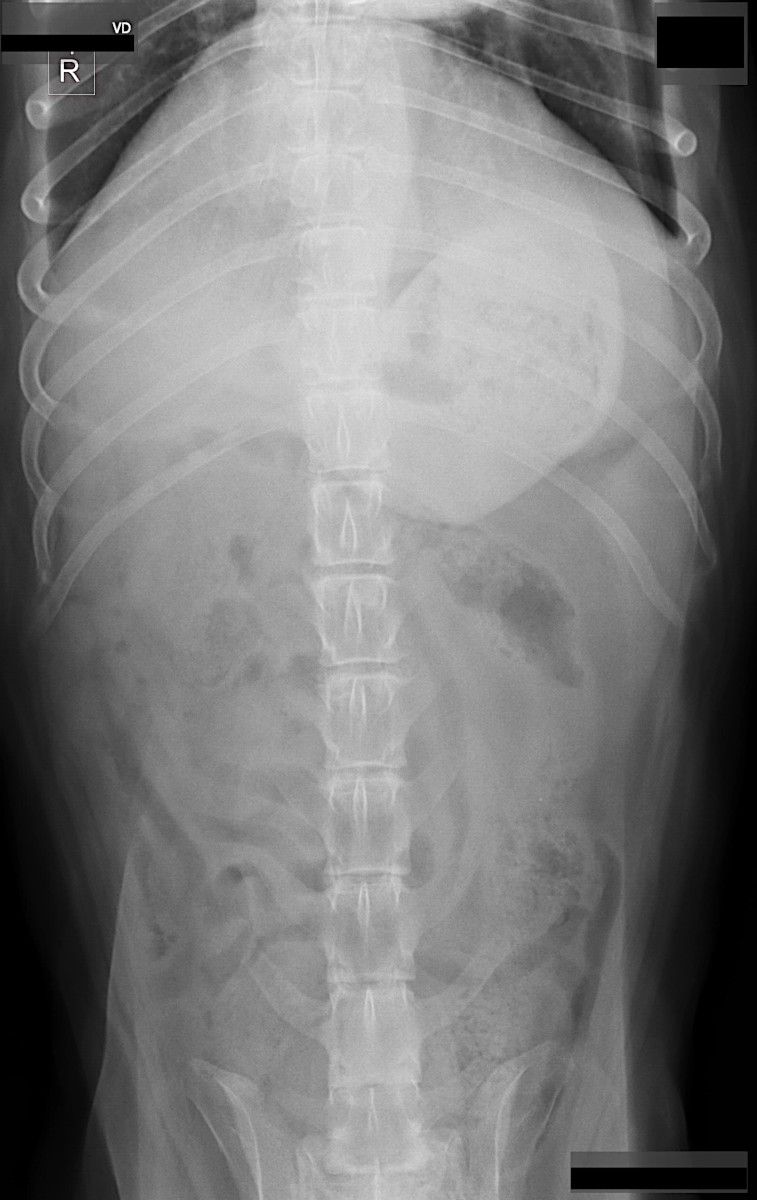

Simba had some upper abdomen tenderness when the vet checked him out, so some blood work and x-rays were done. Blood work indicated that Simba was anemic, which raised a concern about something going on with his spleen. There didn’t seem to be anything strikingly unusual on the x-rays. Liver and at least part of his spleen appeared normal, but that doesn’t mean there isn’t anything wrong. He also has some osteoarthritis going on in his thoracic spine area.